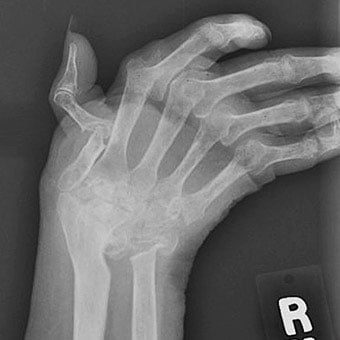

Joint deformity can occur from chronic rheumatoid arthritis. Deformity in rheumatoid arthritis occurs because the unchecked inflammation leads to erosions of cartilage and bone as well as ligament loosening (laxity).

- Early diagnosis and treatment of rheumatoid arthritis are critical to prevent permanent joint damage and joint deformity.

Usually, but not always, rheumatoid arthritis affects many joints. Classically, RA affects the small joints of the hands and wrists and balls of the feet. Also, not uncommonly, knees, elbows, hips, ankles, and shoulders can be inflamed.

- Accordingly, the small joints of the hands, wrists, and feet are commonly affected.

A joint is the area where two bones meet. Within joints is a tissue called cartilage that acts as a cushion between two bony surfaces. Synovial fluid within joints protects them and helps facilitate movement. Synovial fluid is secreted by the inner lining of the joint called the synovial membrane. Hand arthritis occurs when there is inflammation in one or more joints of the hand and wrist. There are over 100 types of arthritis. A few of the common types of arthritis that affect the hands are osteoarthritis, rheumatoid arthritis, post-traumatic arthritis (arthritis as a result of an injury), psoriatic arthritis and gout. The two most common types of arthritis that affect the hands are osteoarthritis and rheumatoid arthritis. Hand osteoarthritis occurs when there is wear and tear of one or more joints of the hand as seen with increasing age. Rheumatoid arthritis occurs when the body’s immune system attacks the joints of the hand.